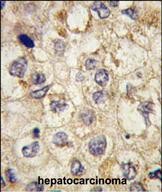

- Formalin-fixed and paraffin-embedded human hepatocarcinoma tissue reacted with SSR1 antibody (N-term) (Cat.#P30232), which was peroxidase-conjugated to the secondary antibody, followed by DAB staining. This data demonstrates the use of this antibody for immunohistochemistry; clinical relevance has not been evaluated.